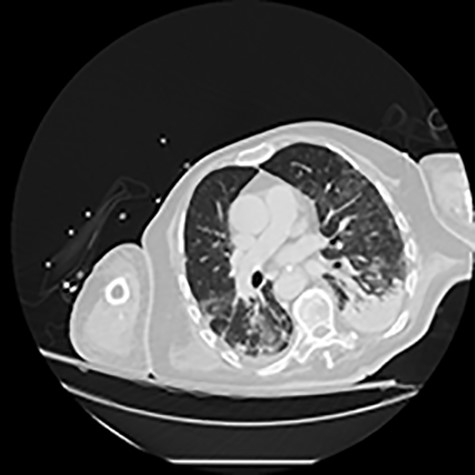

He initially received supportive treatment but clinically deteriorated 48 h post admission, developing hypoxemic respiratory failure. His chest X-ray and computed tomography (CT) of the chest at that time revealed multiple ground glass opacities and areas of consolidation (Fig. 1). He was transferred to the intensive care unit (ICU), where he was intubated, and his treatment was escalated to broad-spectrum antibiotics and hydroxychloroquine. He had been on prophylactic enoxaparin (6000 IU/once daily) since the beginning of his hospital admission. Laboratory results upon ICU transfer are summarized in Table 1. In regard to his coagulation parameters, he had a prolonged activated partial thromboplastin time (aPTT), increased D-dimer and fibrinogen. His platelets were within normal range.

CT of the chest showing bilateral multiple ground glass opacities and areas of consolidation consistent with COVID-19 pneumonia.